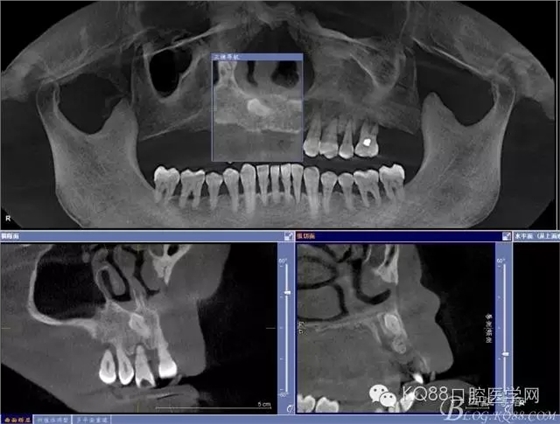

患者 男 57歲

主訴:右上后牙缺失要求修復(fù)

現(xiàn)病史:患者右上前牙松動,右上后牙缺失,要求固定修復(fù)

既往史:吸煙史,拔牙史,其他無異常

檢查:11、12、13Ⅲ度松動,牙齦退縮,根面暴露,14、15、16、17缺失,余牙不同程度牙齦退縮。

輔助檢查:ct示骨密度良好,11 12區(qū)域骨下有一水平向埋伏牙,15 16區(qū)域骨高度2.5-3mm,骨寬度6-9mm。

診斷:牙列缺損 牙周炎